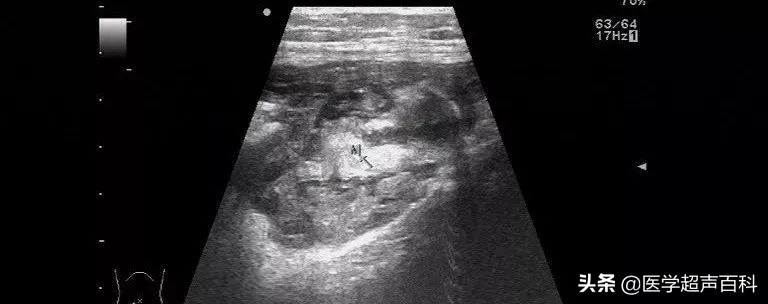

当肿瘤破裂时,可表现为右下腹形态不规则囊实混合性包块,边界清楚,内部回声不均质,其后方回声可有增强;当发生腹腔其他部位种植时,种植部位声像图表现与右下腹包块的声像图表现相似。